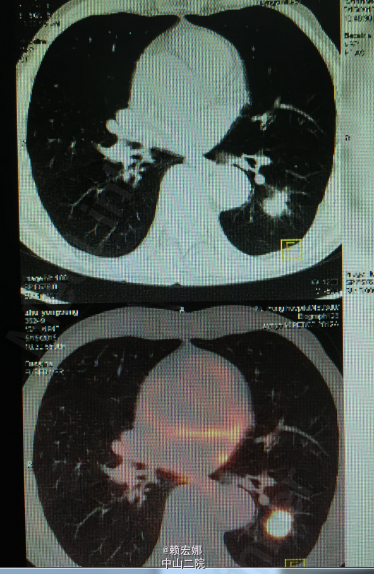

患者,男,67岁,咳嗽、咳痰1年余。外伤后查体发现左下肺占位1周余。

胸廓未见异常,胸骨无压痛,乳房正常对称。呼吸运动未见异常,肋间隙未见异常,语颤未见异常。叩诊清音,呼吸规整,双肺呼吸音清晰,双肺未闻及干湿性啰音,无胸膜摩擦感。心前区无隆起,心尖搏动未见异常,心浊音界未见异常。浙江省永嘉县人民医院胸片提示左下肺结节 ,CT提示左下肺占位 ,考虑周围型肺癌可能。我院PET-CT:1、左下肺背段结节状高代谢病灶,考虑为左肺癌;2、纵膈内多发淋巴结炎性增生;双肺门及纵膈内未见恶性肿瘤征象;3、颅内双侧侧脑室旁脑白质变性;脑桥右侧陈旧性脑梗塞灶;右侧筛窦轻度炎症;双侧颈部及双侧腋窝多发淋巴结炎性增生;4、双肺尖多发陈旧性炎症,双肺尖多个小肺大泡;双上肺肺气肿;5、肝左内叶小囊肿;左肾小囊肿;前列腺钙化灶;6、全身其他部位未见明显异常。

患者肺癌诊断明确,术前检查未见明显禁忌症,胸腔镜下行左下肺癌根治术,手术顺利,术后病理:1、(左下肺)浸润性肺腺癌,实体为主型;2、支气管及肺切缘未见癌残留;3、(5 7 9 10 11组)淋巴结未见癌转移(0/4 0/5 0/2 0/1 0/1).术后予重症监护,抗感染、营养支持等对症支持治疗。